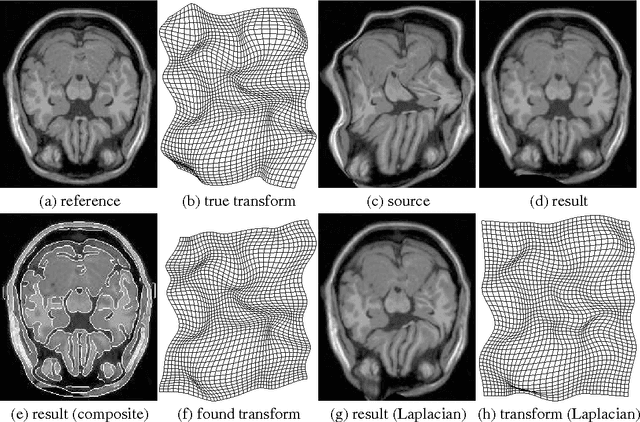

Abstract:We introduce an adaptive regularization approach. In contrast to conventional Tikhonov regularization, which specifies a fixed regularization operator, we estimate it simultaneously with parameters. From a Bayesian perspective we estimate the prior distribution on parameters assuming that it is close to some given model distribution. We constrain the prior distribution to be a Gauss-Markov random field (GMRF), which allows us to solve for the prior distribution analytically and provides a fast optimization algorithm. We apply our approach to non-rigid image registration to estimate the spatial transformation between two images. Our evaluation shows that the adaptive regularization approach significantly outperforms standard variational methods.